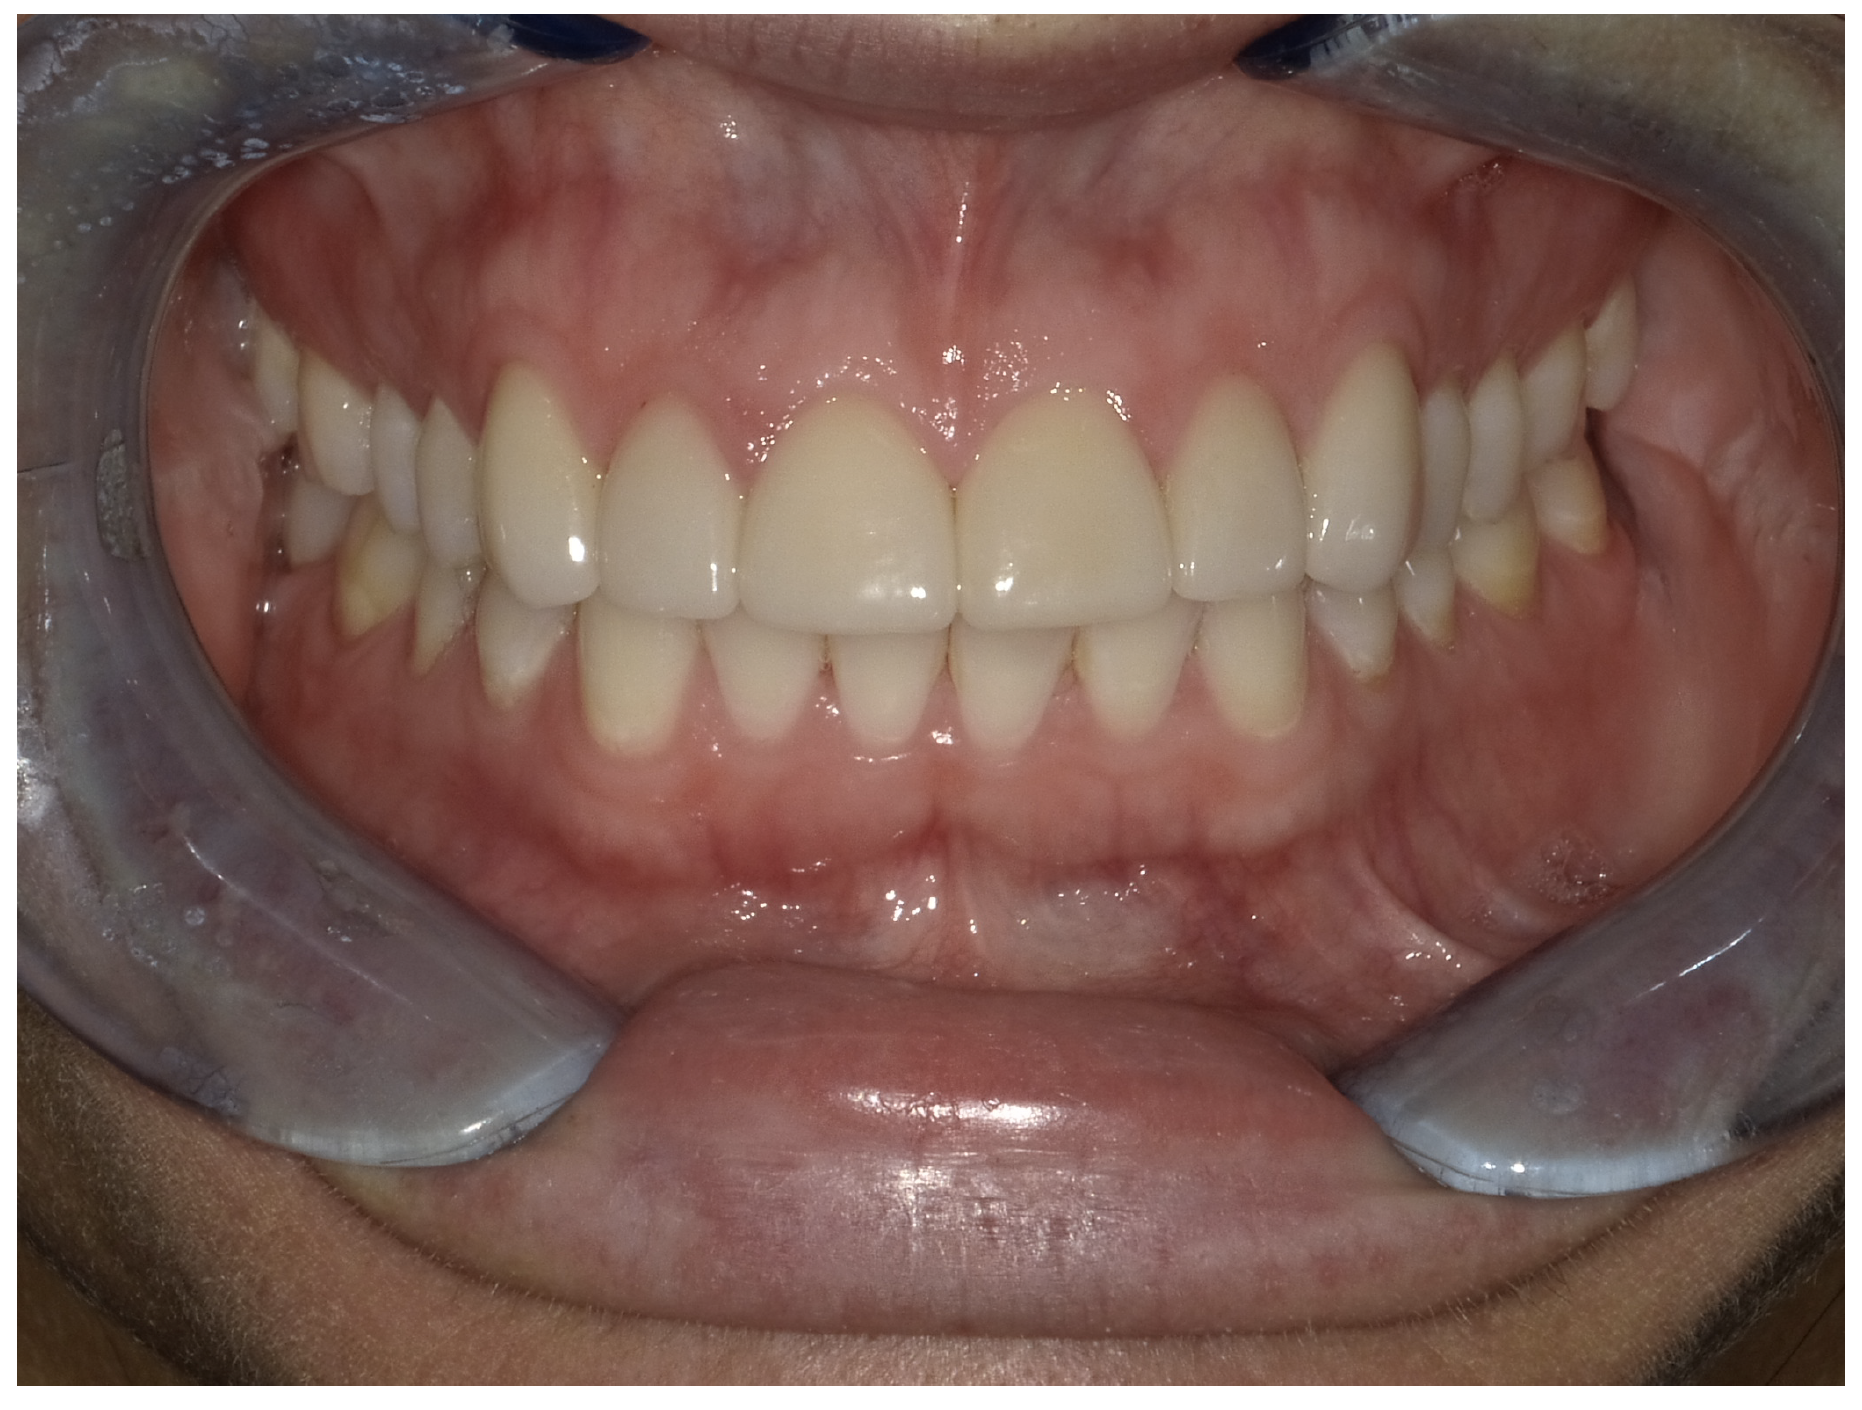

For the case in Figure 9 through Figure 11, the patent presented for an initial consultation with bonding completed on teeth Nos. 7 through 10 a few years prior with a chief complaint of not liking the way the resin bonding looked and how it was wearing. Up to this point, the bonding had repeatedly chipped and been repaired three times already. The patient's canines also exhibited signs of incised wear and flattening, which she did not like. Based on the patient's goals for her smile and her financial budget, she elected to have porcelain veneers completed on teeth Nos. 6 through 11. The total esthetics of the case design were somewhat limited given that the patient's esthetic zone included her posterior teeth and mandibular anterior teeth. Therefore, the color and characteristics of the veneers had to match her existing dentition closely.

In another case, the patient presented with very thick, bulky, over-contoured veneers done on teeth Nos. 7 through 10 when she was a teenager. There also was some recession and staining at the margins (Figure 12). The clinician decided to restore teeth Nos. 6 through 11. A preparation design was required with provisionals removed. As tooth structure could not be regrown, the practitioner made the best of the situation. There was good gum health, which is important for isolation and marginal seal. The clinician cemented with a universal, doing six units at one time. Minimal cleanup was required. At a 1-month follow-up visit, although tissue still was settling in, the contours were natural. After a year (Figure 13), the gum filled in nicely and was in excellent health, and there was good color stability and seamless marginal integrity.